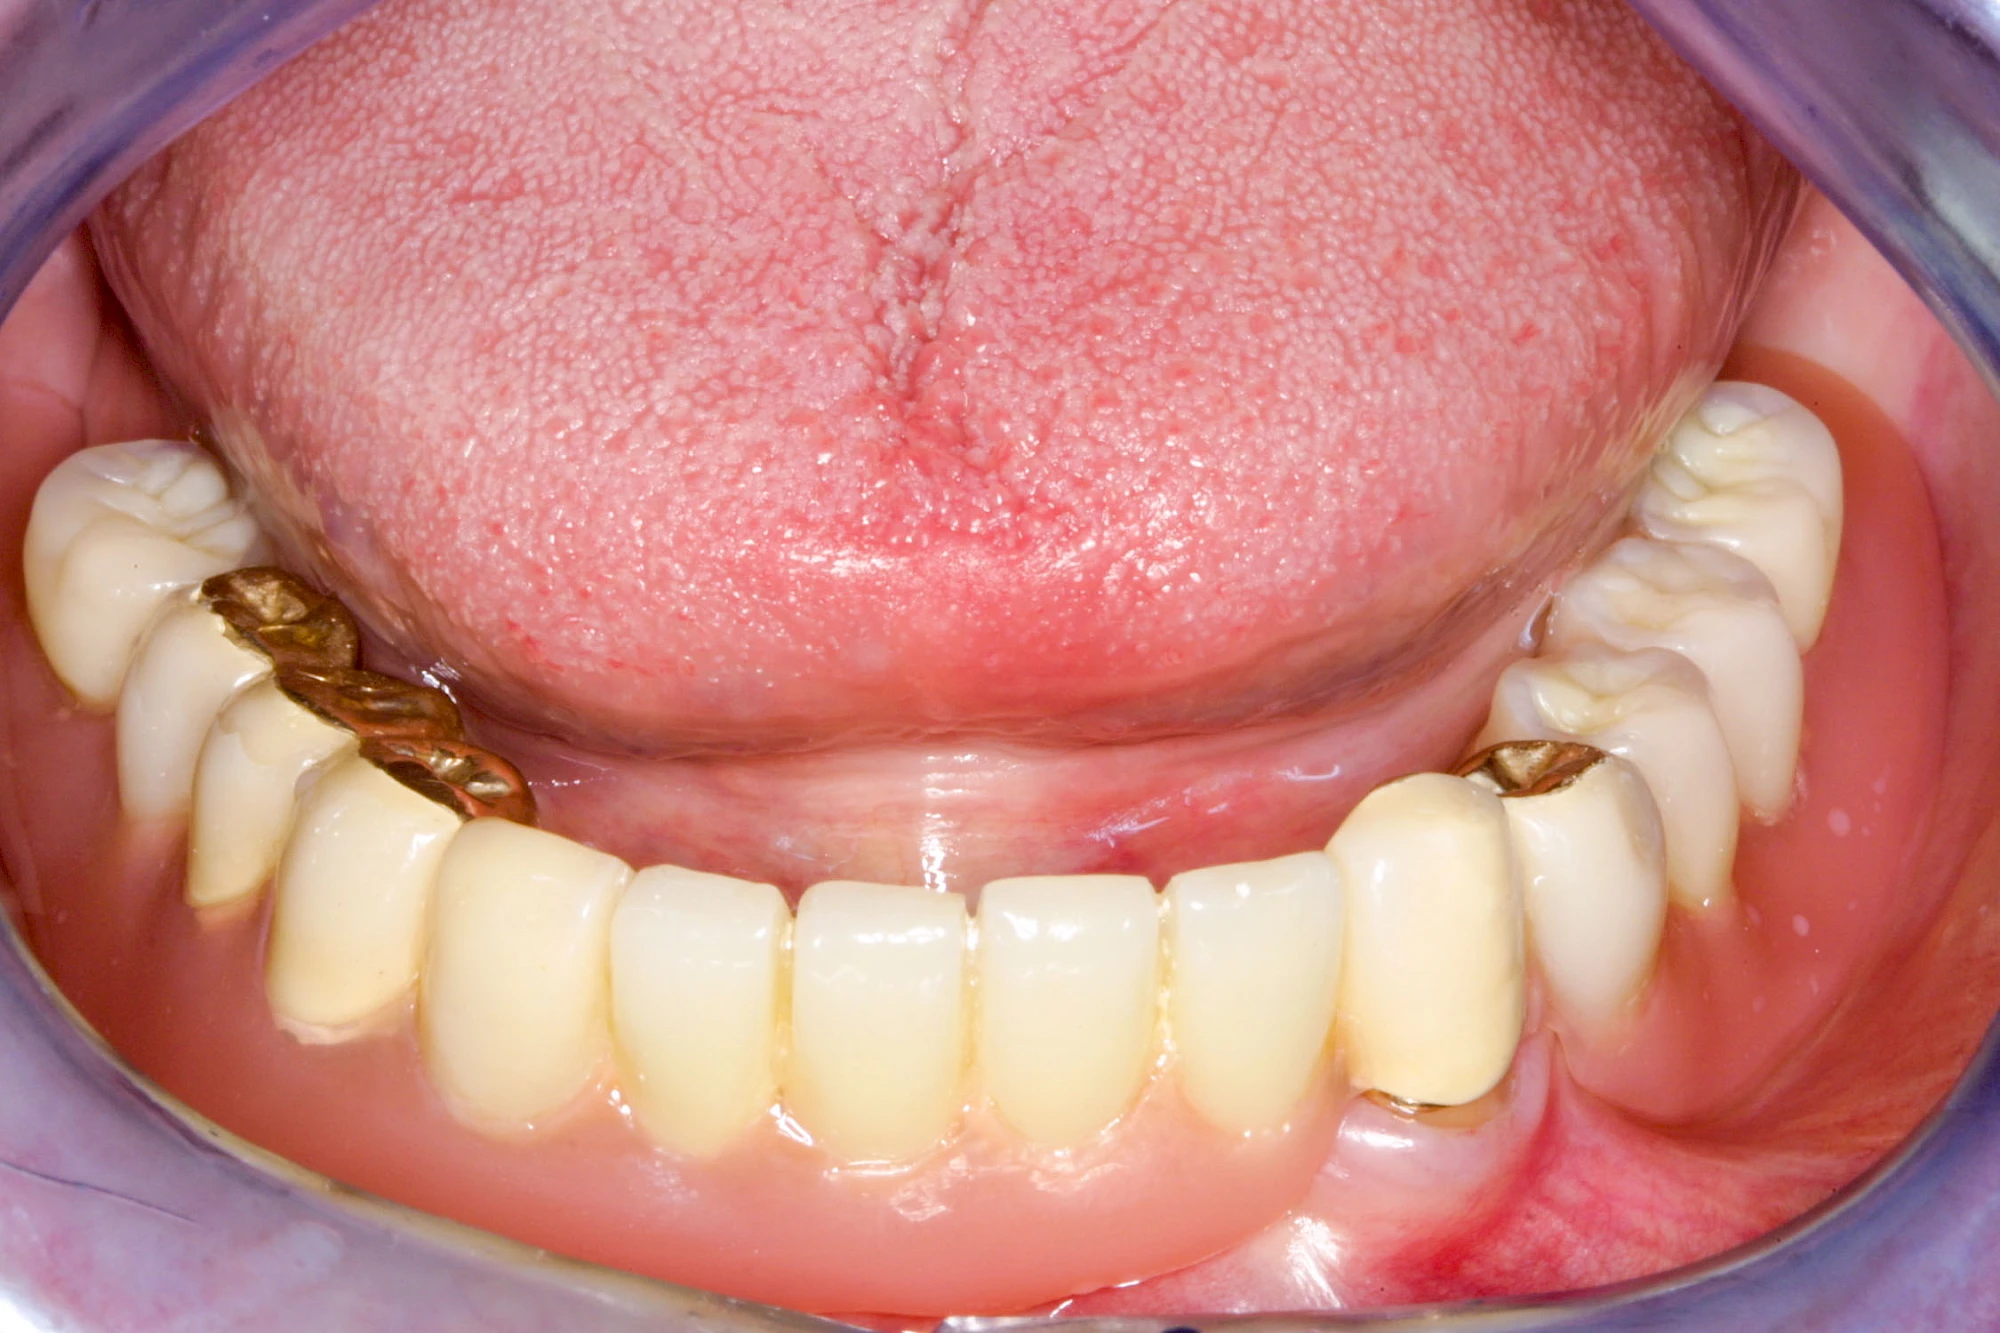

Fehlen einzelne Zähne und die Nachbarzähne sind unbeschadet oder gut zahnärztlich versorgt, werden immer häufiger Implantate gewählt, um die Lücken zu schließen. Auch bei größeren oder verteilten Lücken, wenn keine herausnehmbare Prothese gewünscht ist, werden Implantate für Kronen- bzw. Brückenversorgungen gesetzt. In Einzelfällen entscheiden sich sogar zahnlose Patienten für eine festsitzende Versorgung auf Implantaten.

Varianten zur Verankerung von festsitzendem Zahnersatz auf Implantaten

Implantate: Prothesen

Bei herausnehmbaren Prothesen werden Implantate eingesetzt, um den Halt und den Tragekomfort der Prothesen zu verbessern. Dazu kommen verschiedene Verbindungselemente zum Einsatz:

Neben rein implantat-getragenen zahnärztlichen Versorgungen werden bei herausnehmbaren Prothesen Implantate auch in Sinne einer "strategischen Pfeilervermehrung" ergänzend zu eigenen Zähnen zur Verankerung eines Zahnersatzes genutzt.

Varianten zur Verankerung von abnehmbarem Zahnersatz auf Implantaten